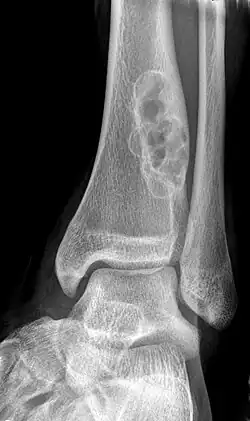

X-ray of nonossifying fibroma of distal tibia. | |

Diagnosis is by X-ray or MRI, usually when investigating a person for something else.[2] Medical imaging typically shows a well defined radiolucent lesion, with a distinct multilocular appearance, sometimes looking like bubbles.[2] It is usually around 1–2 cm in size, but be as large as 7 cm.[3] They consist of foci consist of collagen rich connective tissue, fibroblasts, histiocytes and osteoclasts.[2] Usually no treatment is required.[1] Surgical curettage and bone grafting may be required if it is large.[3]

It is usually diagnosed by x-ray or MRI, when investigating another problem.[1] The tumor presents as a well defined radiolucent lesion, with a distinct multilocular appearance, sometimes looking like a "soap bubble".[5] If small and no symptoms, then biopsy is not needed.[1]